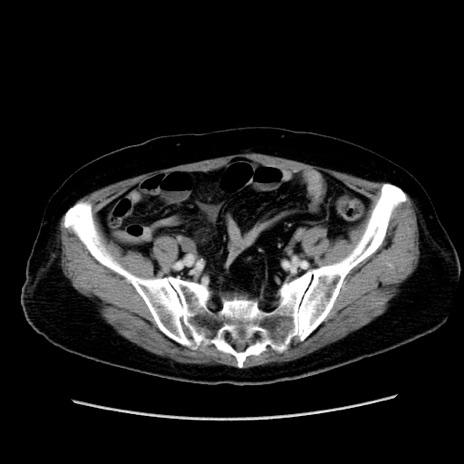

症例19(横断像)

【症例】80歳代女性

【主訴】下腹部痛

【現病歴】約8時間前より下腹部痛の出現あり、救急外来受診。

【既往歴】両側付属器切除

【身体所見】意識清明、下腹部正中に手術痕あり、その部位に一致して圧痛と反跳痛あり。腸蠕動音は亢進。

【データ】WBC 9300、CRP 0.15